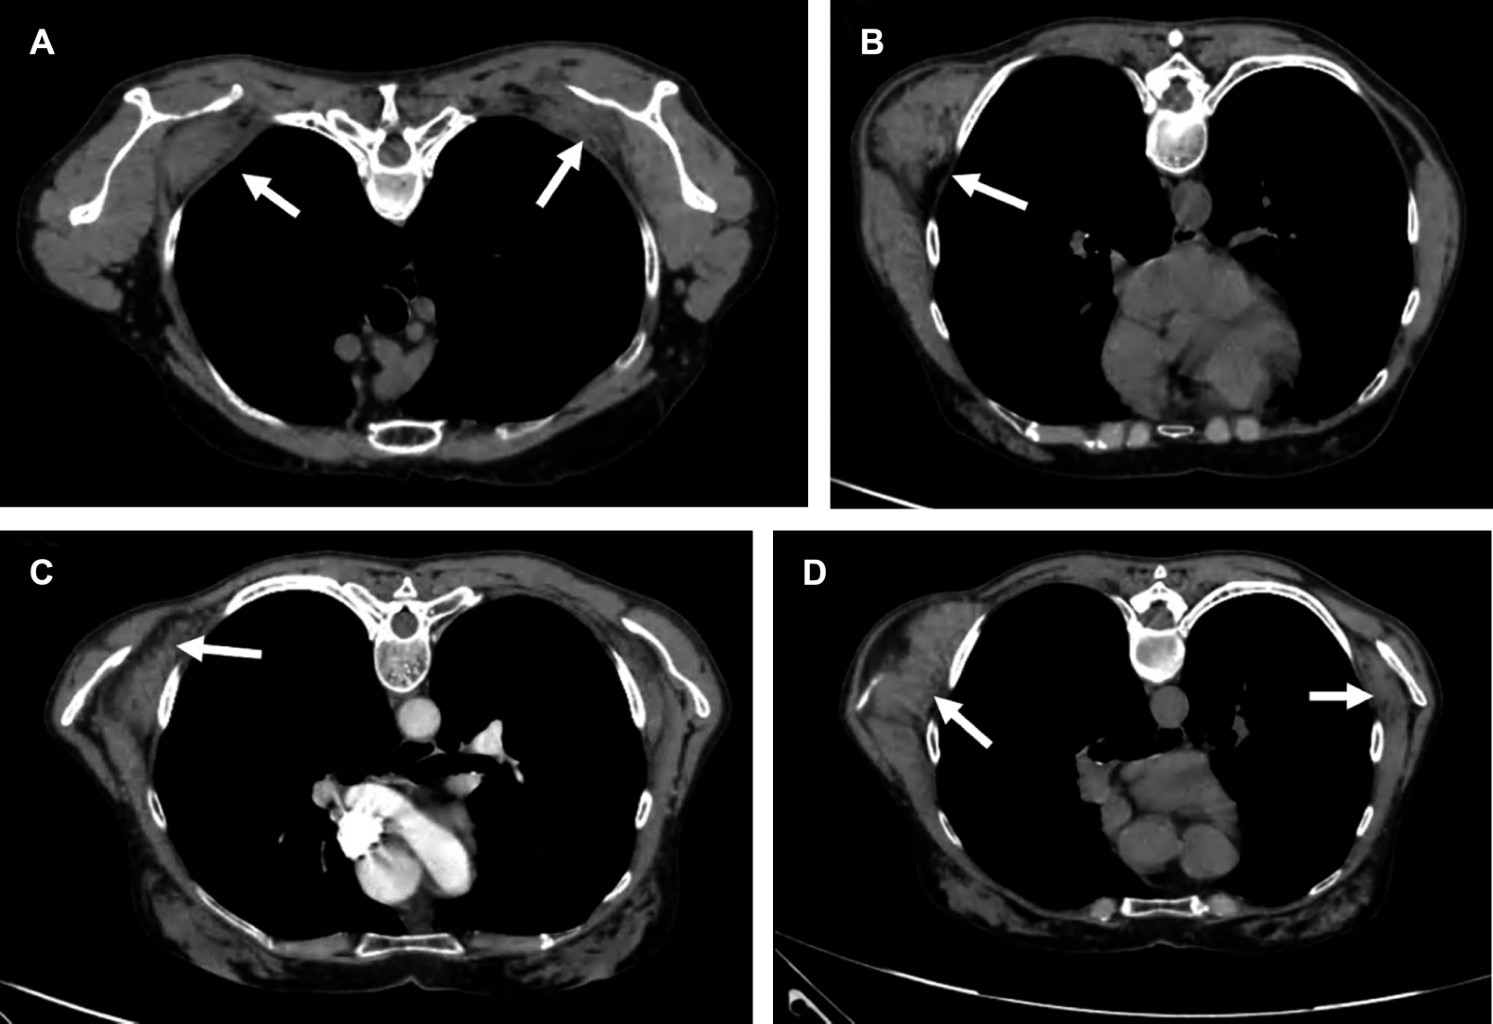

Paciente femenino de 60 años, ama de casa, acude por presentar abultamiento de cinco años de evolución en región escapular derecha, que le ocasiona discreta molestia al efectuar limpieza en el hogar. A la exploración se observa masa de consistencia ahulada en ángulo inferior de escápula derecha prominente, con dimensiones de 7 × 5 cm (Figura 1A-C), no dolorosa al movimiento, con sensación de frote a los desplazamientos de ambas escápulas, con arcos de movilidad de hombros completos y sensibilidad normal; el resto de la exploración es normal. Con diagnóstico presuntivo de elastofibroma dorsi. Se solicita tomografía computarizada (Figuras 1, 2 y 3) que confirma elastofibromas dorsi bilaterales; se propone cirugía, la cual rechaza.

La ecografía, la tomografía computarizada y la resonancia magnética confirman el diagnóstico.4 En la ecografía se observa un patrón alternante, de tipo fasciculado o laminar, de líneas hipo e hiperecogénicas paralelas a la pared torácica; la señal Doppler suele ser negativa. La TC muestra alternancia de tejido adiposo con densidad grasa y de tejido fibroso con densidad muscular, que no realza con medios de contraste. La resonancia magnética es de elección para llegar al diagnóstico presentando patrón alternante de tejido adiposo y fibroso; en T1 y T2 el tejido fibroso da señales de baja intensidad similares a las del músculo. El tejido adiposo da señales de alta intensidad en T1 y señales intermedias en T2. La biopsia se reserva para los casos sospechosos que no presentan el patrón característico.5